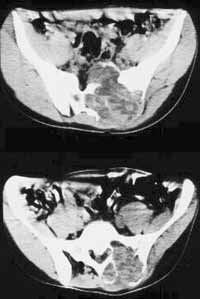

Рис. 2. Аневризматическая костная киста крестца. Компьютерная томограмма.

Новости лучевой диагностики 2001 1-2: 22-24